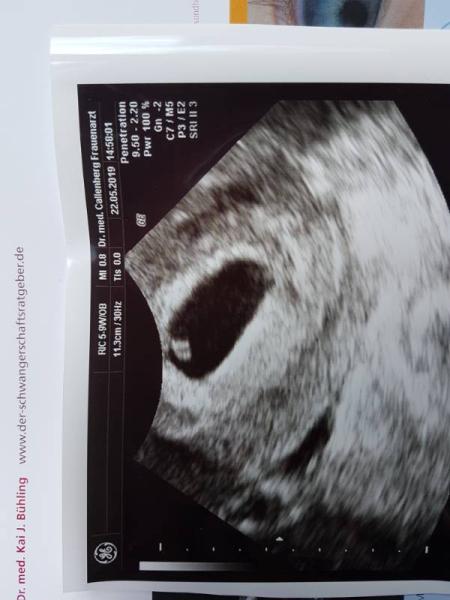

Leute heute habe ich 1 Tag früher als geplant mein Baby sehen können. SSW 6+2 das Herzchen pocht fleißig. Ich hatte 4 Tage lang Schmierblutung bräunlich. Mein FA hatte sofort Zeit für mich. Es war so emotional als ich das Herzchen pochen sah und gesagt bekommen habe das alles in Ordnung ist.

Bild zu